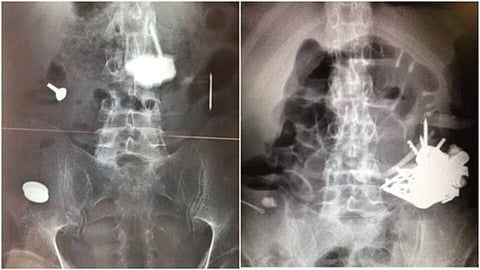

നാല് തവണയാണ് പല ഘട്ടങ്ങളിലായി ശസ്ത്രക്രിയ നടത്തിയത്. വയറ്റില് നടത്തിയ സ്കാനിങ്ങില് ലോഹങ്ങള് ആന്തരികാവയവങ്ങളില് കൂടിച്ചേര്ന്ന് ദ്വാരമുണ്ടാക്കിയ നിലയിലായിരുന്നു.

ബിഎംജി റിപ്പോര്ട്ട് അനുസരിച്ച്, 2012 മെയ് മാസത്തിലാണ് ലാണ് ഇദ്ദേഹം ആദ്യമായി ആശുപത്രിയില് എത്തിയത്. ഗുരുതരമായ മനോരോഗമുള്ള രോഗി വയറുവേദനയെ തുടര്ന്നാണ് ആശുപത്രിയില് എത്തിയത്. പരിശോധനയില് വയറ്റിനുള്ളില് ലോഹ വസ്തുക്കള് കണ്ടെത്തി. തുടര്ന്ന് എന്ഡോസ്കോപ്പിയിലൂടെ ഇവ നീക്കം ചെയ്തു. ലോഹവസ്തുക്കള് പൂര്ണമായും നീക്കം ചെയ്യാനാകാത്തതിനെ തുടര്ന്ന് എട്ട് മാസത്തിനു ശേഷം രോഗിയെ വീണ്ടും ആശുപത്രിയില് പ്രവേശിപ്പിച്ച് ശസ്ത്രക്രിയയ്ക്ക് വിധേയനാക്കി. നഖങ്ങള്, കത്തികള്, സ്ക്രൂ, ആണികള്, സ്പൂണ് കഷ്ണങ്ങള്, സ്ക്രൂഡ്രൈവറിന്റെ ഭാഗങ്ങള്, കല്ലുകള്, നാണയങ്ങള് എന്നിവയൊക്കെയാണ് ശസ്ത്രക്രിയയിലൂടെ പുറത്തെടുത്തത്.

ഇത്തരത്തില് കഴിഞ്ഞ അഞ്ച് വര്ഷത്തിനിടയില് ഇദ്ദേഹം നാല് തവണ ശസ്ത്രക്രിയയ്ക്ക് വിധേയനാകുകയും ലോഹ വസ്തുക്കള് പുറത്തെടുത്തതായുമാണ് റിപ്പോര്ട്ടില് പറയുന്നത്.